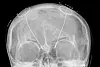

Forskerne har implantert ti elektroder i hjernen på en 36 år gammel kvinne med alvorlig depresjon. Når elektroden fanger opp at hjernen er på vei inn i en depresjon, gir den automatisk et mildt støt.

Deep brain stimulation er en nevrokirurgisk prosedyre der man implanterer elektroder og elektrisk stimulans i hjernen for å behandle ulike nevrologiske sykdommer.

Forskerne har fått den 36 år gamle kvinnen til å vurdere hvor deprimert hun følte seg mens de målte elektriske impulser i hjernen via elektrodene i kraniet.

De oppdaget at symptomene matchet aktivitetsmønstre i amygdala – den mandelformede kjernen i hjernens tinninglapp som blant annet håndterer frykt og forsvarsreaksjoner.

Dermed kunne de stimulere nettopp det området. Elektrodene kunne også fange opp når det var depressiv aktivitet.

Hvorfor nøyer ikke forskerne seg med å sette elektrodene utenpå kraniet, tenker du kanskje?

Men det er mer effektivt å stimulere rett på de områdene i hjernen der lidelsen sitter.

Elektriske signaler utenpå kraniet skal forsere hud og kranium, og det svekker effekten, forteller Martin Balslev Jørgensen.